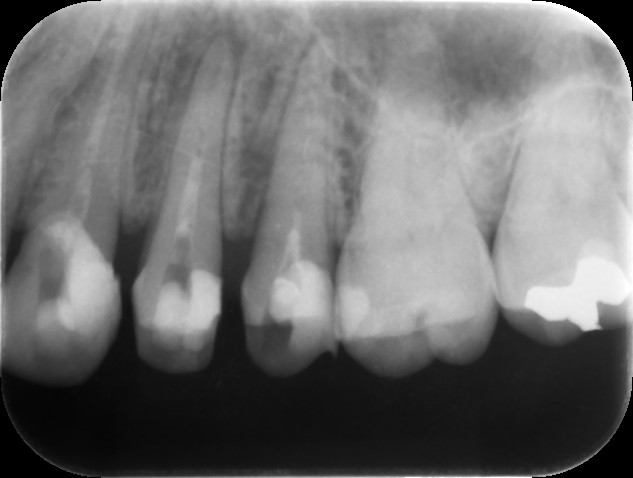

初診時レントゲン。他院で1年以上かけて根管治療を行っているが痛みや歯茎の腫れが引かずに来院。元々は歯髄が生きていた生活歯の抜髄を行ったケース(イニシャルトリート)。同時に3本もの歯を抜髄して長期に根管治療を行う診断に問題があると言わざるを得ない。患者さんは心身ともに疲弊し、歯科治療への不信が高まってしまうのも無理はない。まずは、現状の説明と解決策を提示し、歯科治療への不安を取り除くところから治療が始める。